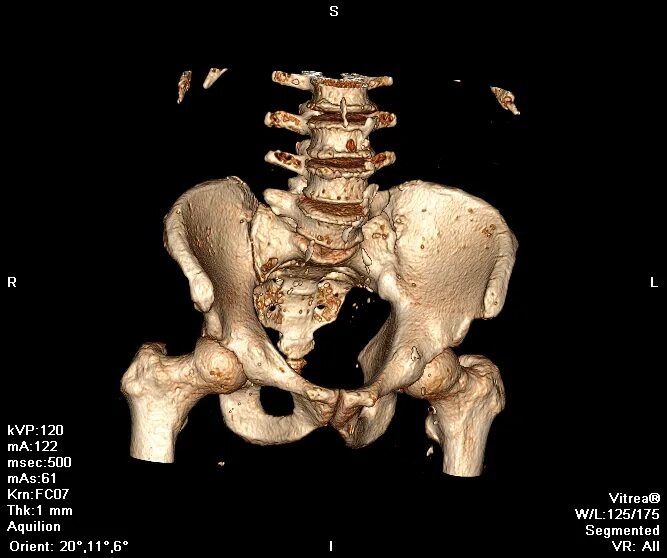

Кт крестцово-копчикового отдела позвоночника. кт пояснично-крестцового отдела позвоночника. кт крестцового отдела позвоночника. кт (мскт) грудного отдела позвоночника.

Позвонки крестца кт. переломы костей таза кт.

Перелом боковых масс крестца кт. перелом 5 крестцового позвонка рентген. перелом латеральной части крестца. перелом поперечного отростка l5 рентген.